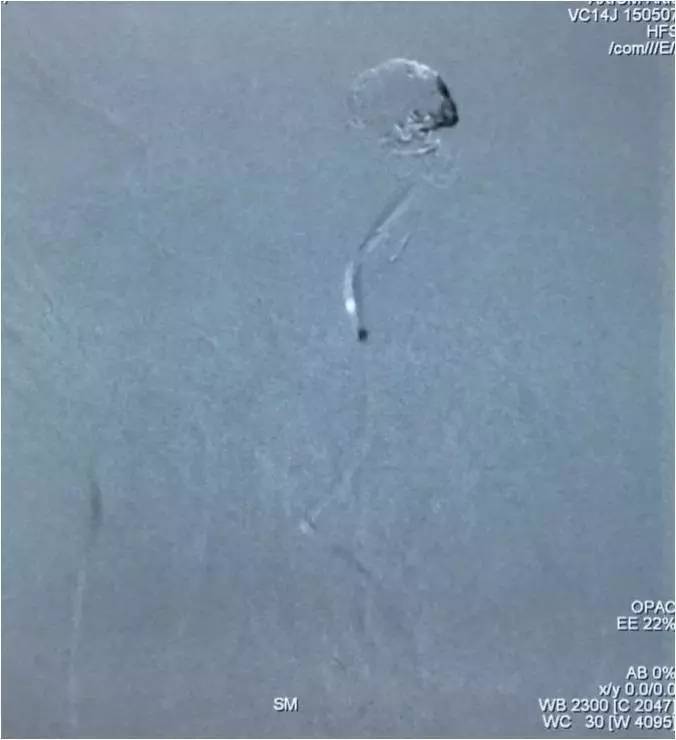

▼Headway17完成左小脑上动脉瘤的栓塞后,再经支架网眼导入右PCA,将第二枚LVIS JR 3.5*23支架跨瘤颈释放入右PCA-基底动脉,如此完成了Y型支架的释放,为基底动脉顶端动脉瘤的栓塞工程摆好了脚手架。

▼微导丝经支架内部弓背进入右PCA,Headway17微导管跟进,目的是加强第二枚支架(穿过了第一枚支架的网眼)的扩张性和贴壁性。